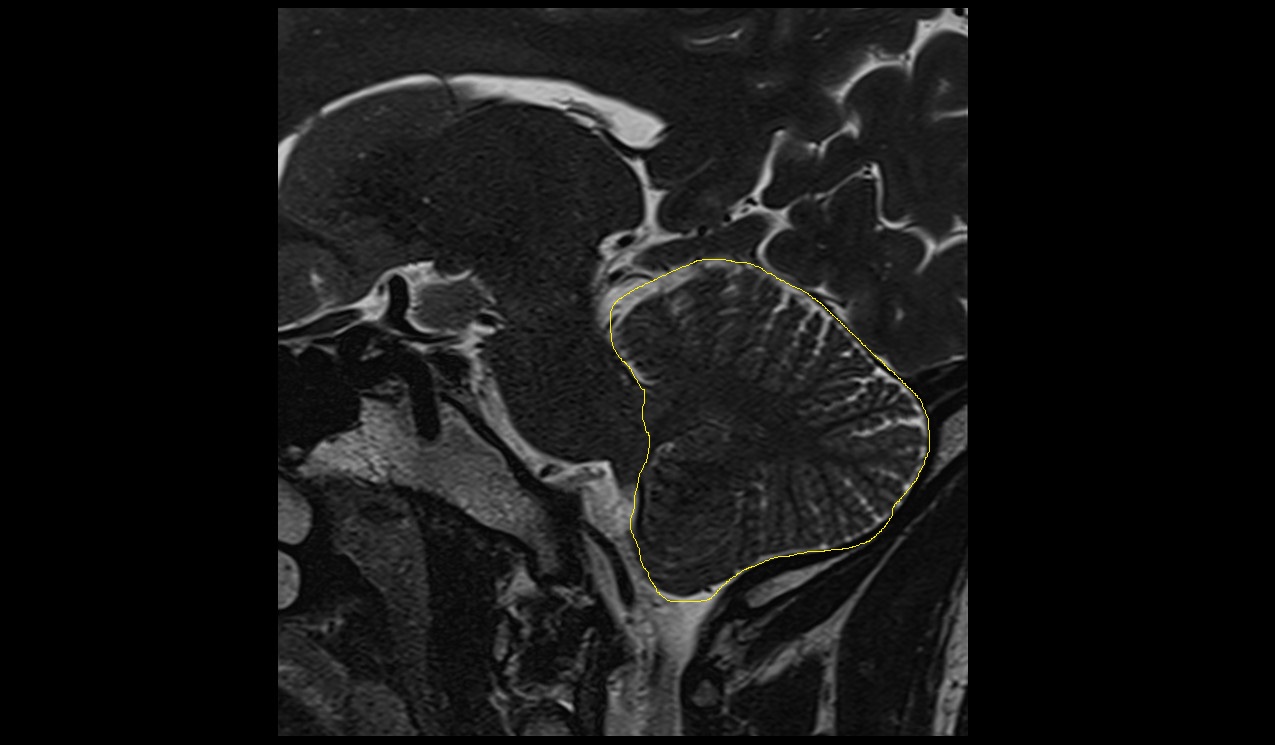

- Cerebellum

- Cerebellar tonsil (H IX)

- Crus I of ansiform lobule of cerebellum

- Crus II of ansiform lobule of cerebellum

- Paramedian lobule (HVII) of cerebellum

- Simple lobule (HVI) of cerebellum